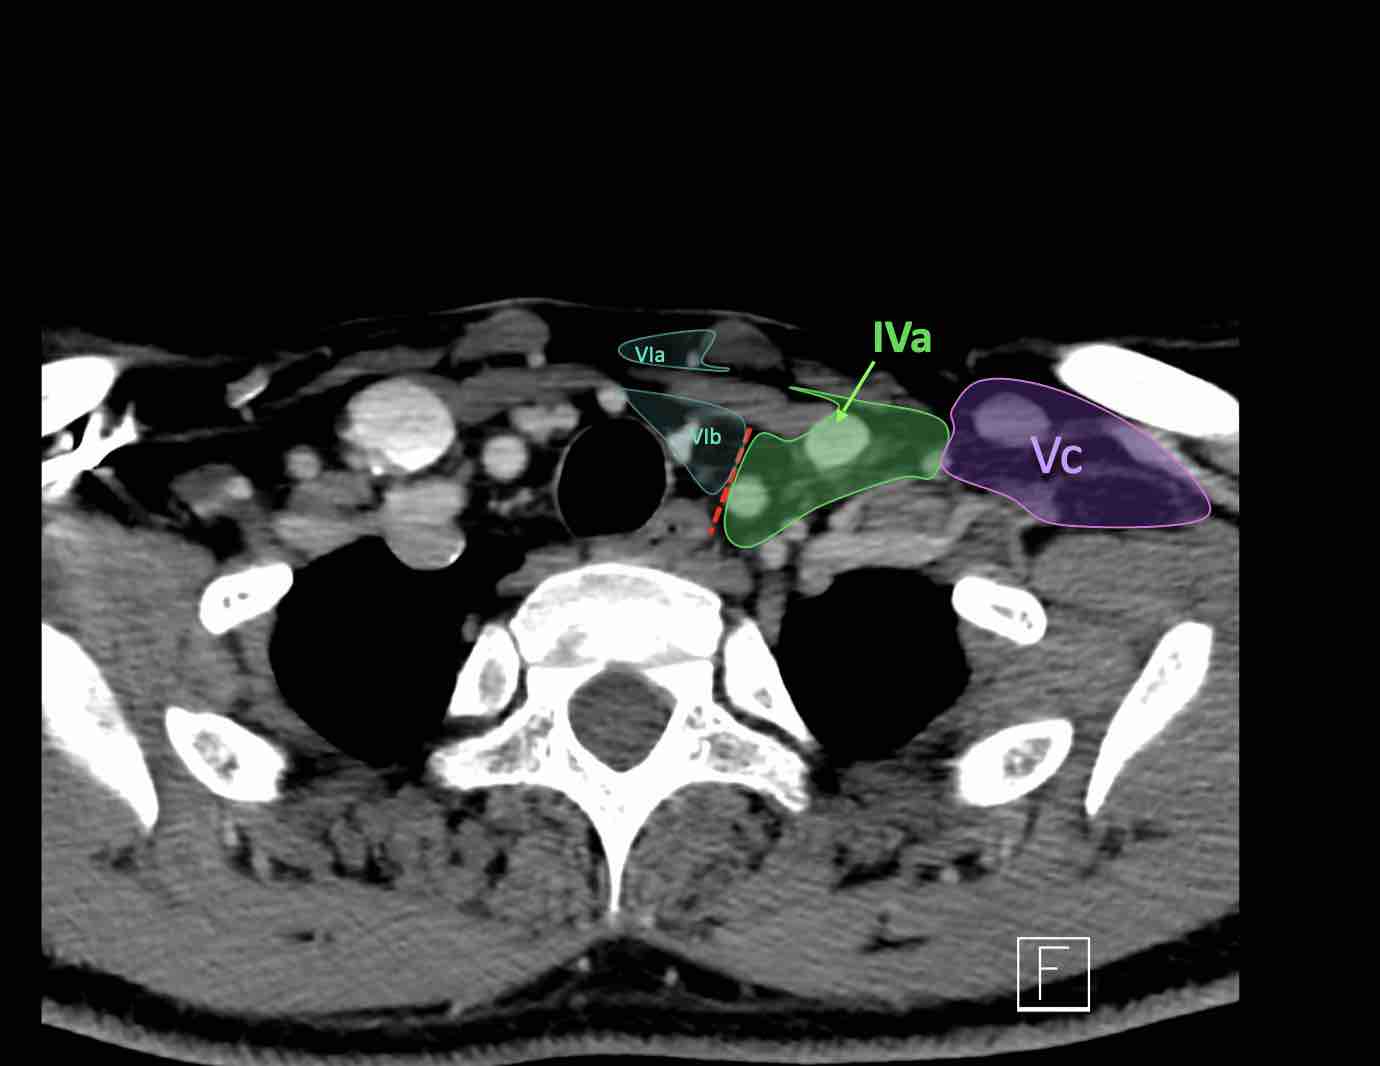

Tầng IVb

Các hạch này có nguy cơ chứa di căn từ các ung thư hạ hầu, thanh quản dưới thanh môn, khí quản, tuyến giáp và thực quản cổ.

V – Tam giác cổ sau và hố thượng đòn

Tầng V chứa các hạch của nhóm tam giác cổ sau nằm ở phía sau cơ ức đòn chũm, xung quanh phần dưới của thần kinh phụ gai sống và các mạch máu cổ ngang.

Các hạch bạch huyết ở tầng V thường liên quan nhất đến các ung thư nguyên phát của vòm hầu, hầu miệng, các cấu trúc da vùng da đầu phía sau và tuyến giáp.

Tầng Vc – Hố thượng đòn

Tầng này chứa các hạch thượng đòn bên nằm trong phần tiếp nối của các hạch tam giác cổ sau (tầng Va và Vb) từ các mạch máu cổ ngang xuống đến giới hạn được xác định tùy ý tại vị trí 2 cm phía trên cán ức.

Tầng này tương ứng một phần với vùng được gọi là hố thượng đòn.

Tầng Vc nhận các bạch mạch hướng tâm từ các hạch tam giác cổ sau (tầng Va và Vb) và thường liên quan hơn đến các khối u vòm hầu [1].